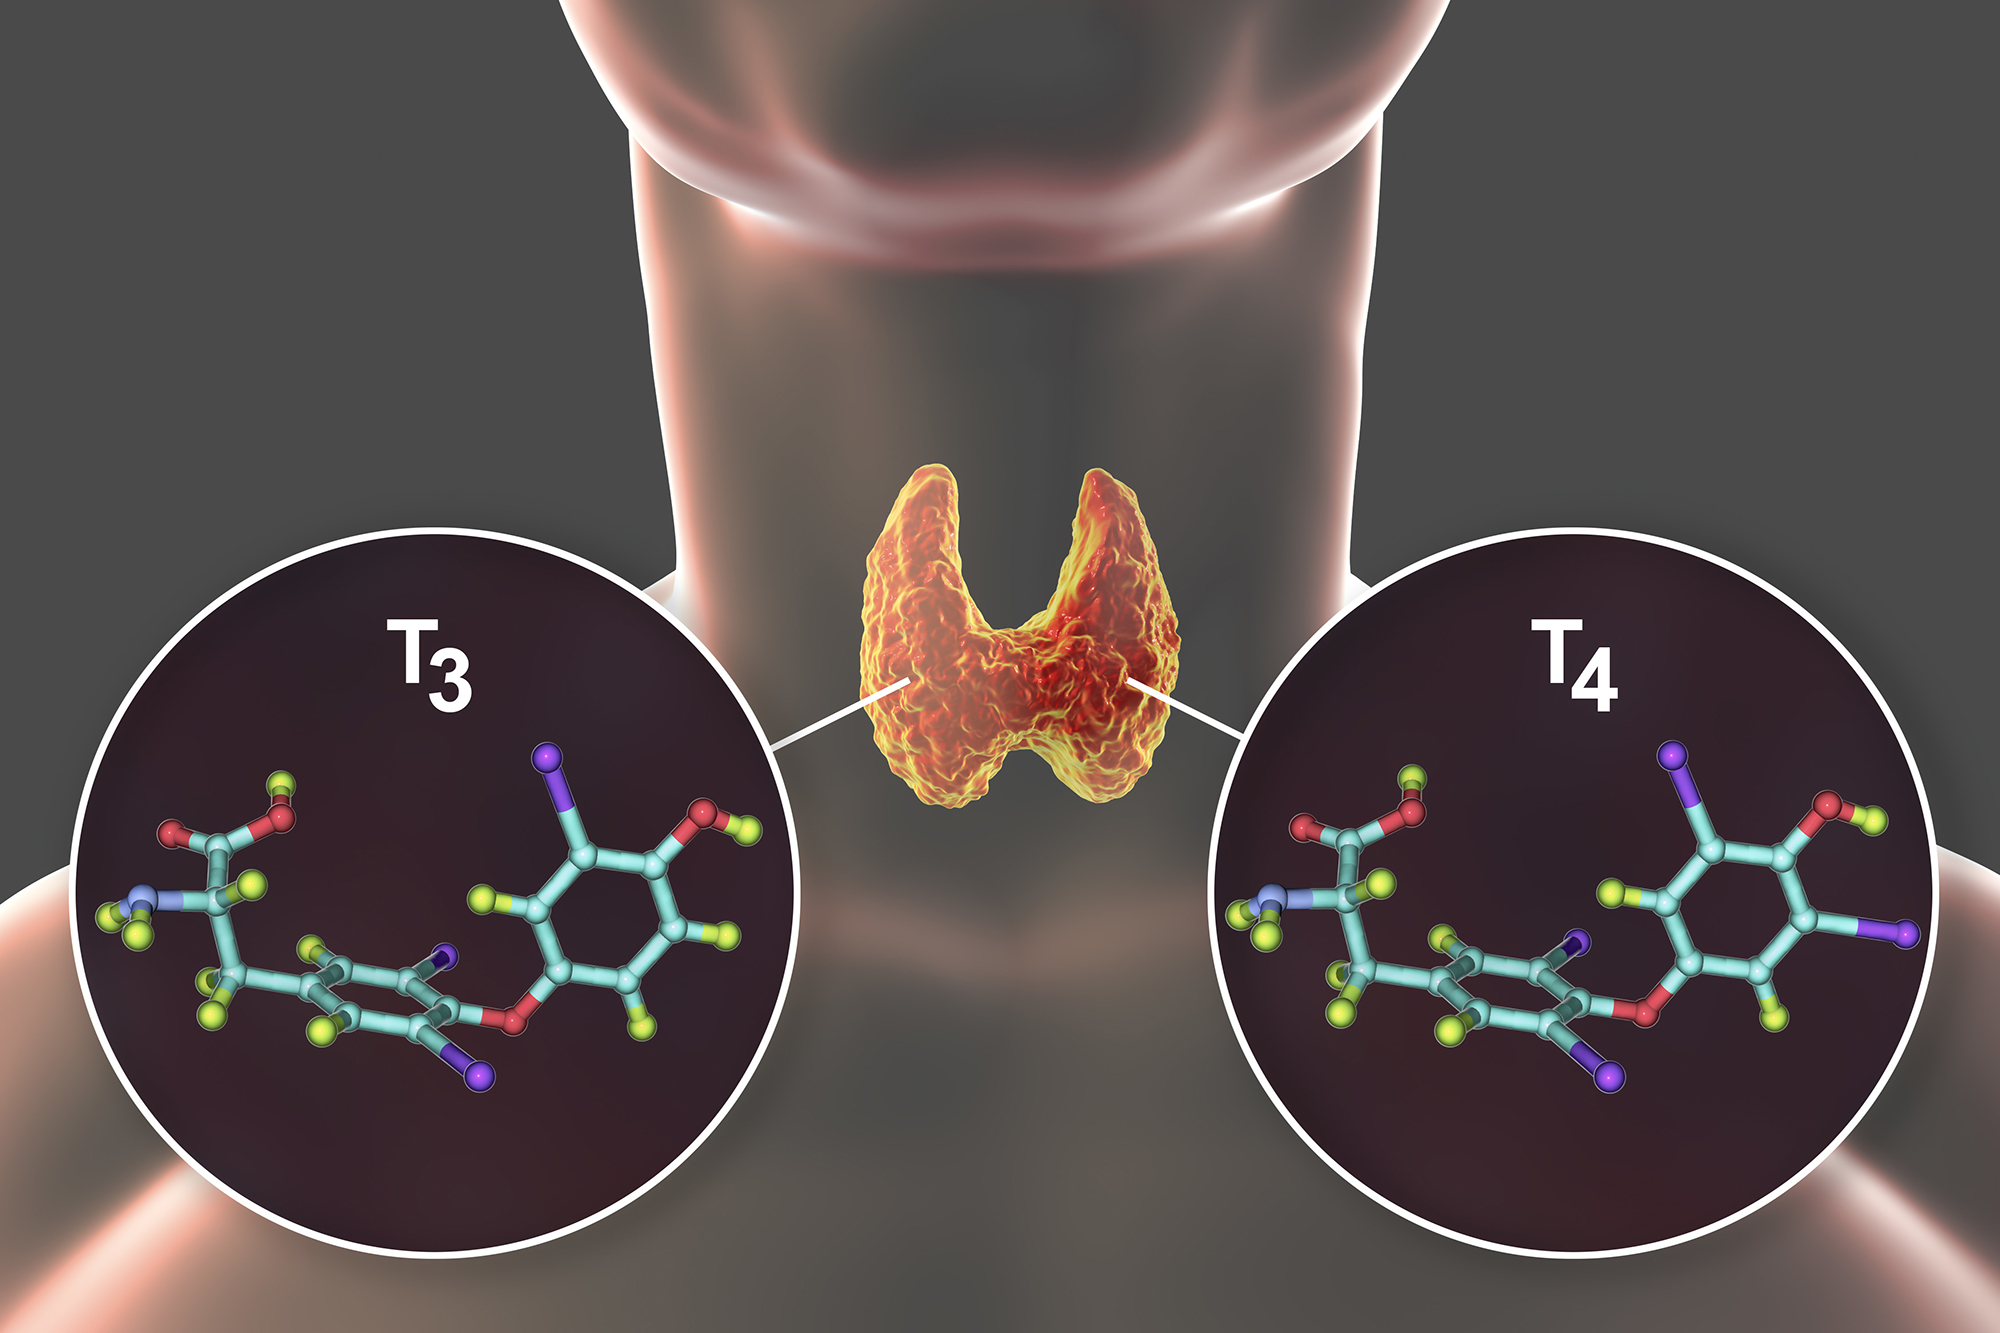

THYROID CLINIC

Thyroid Goiter and Thyroid Nodules

High and Low TSH Thyroid Levels